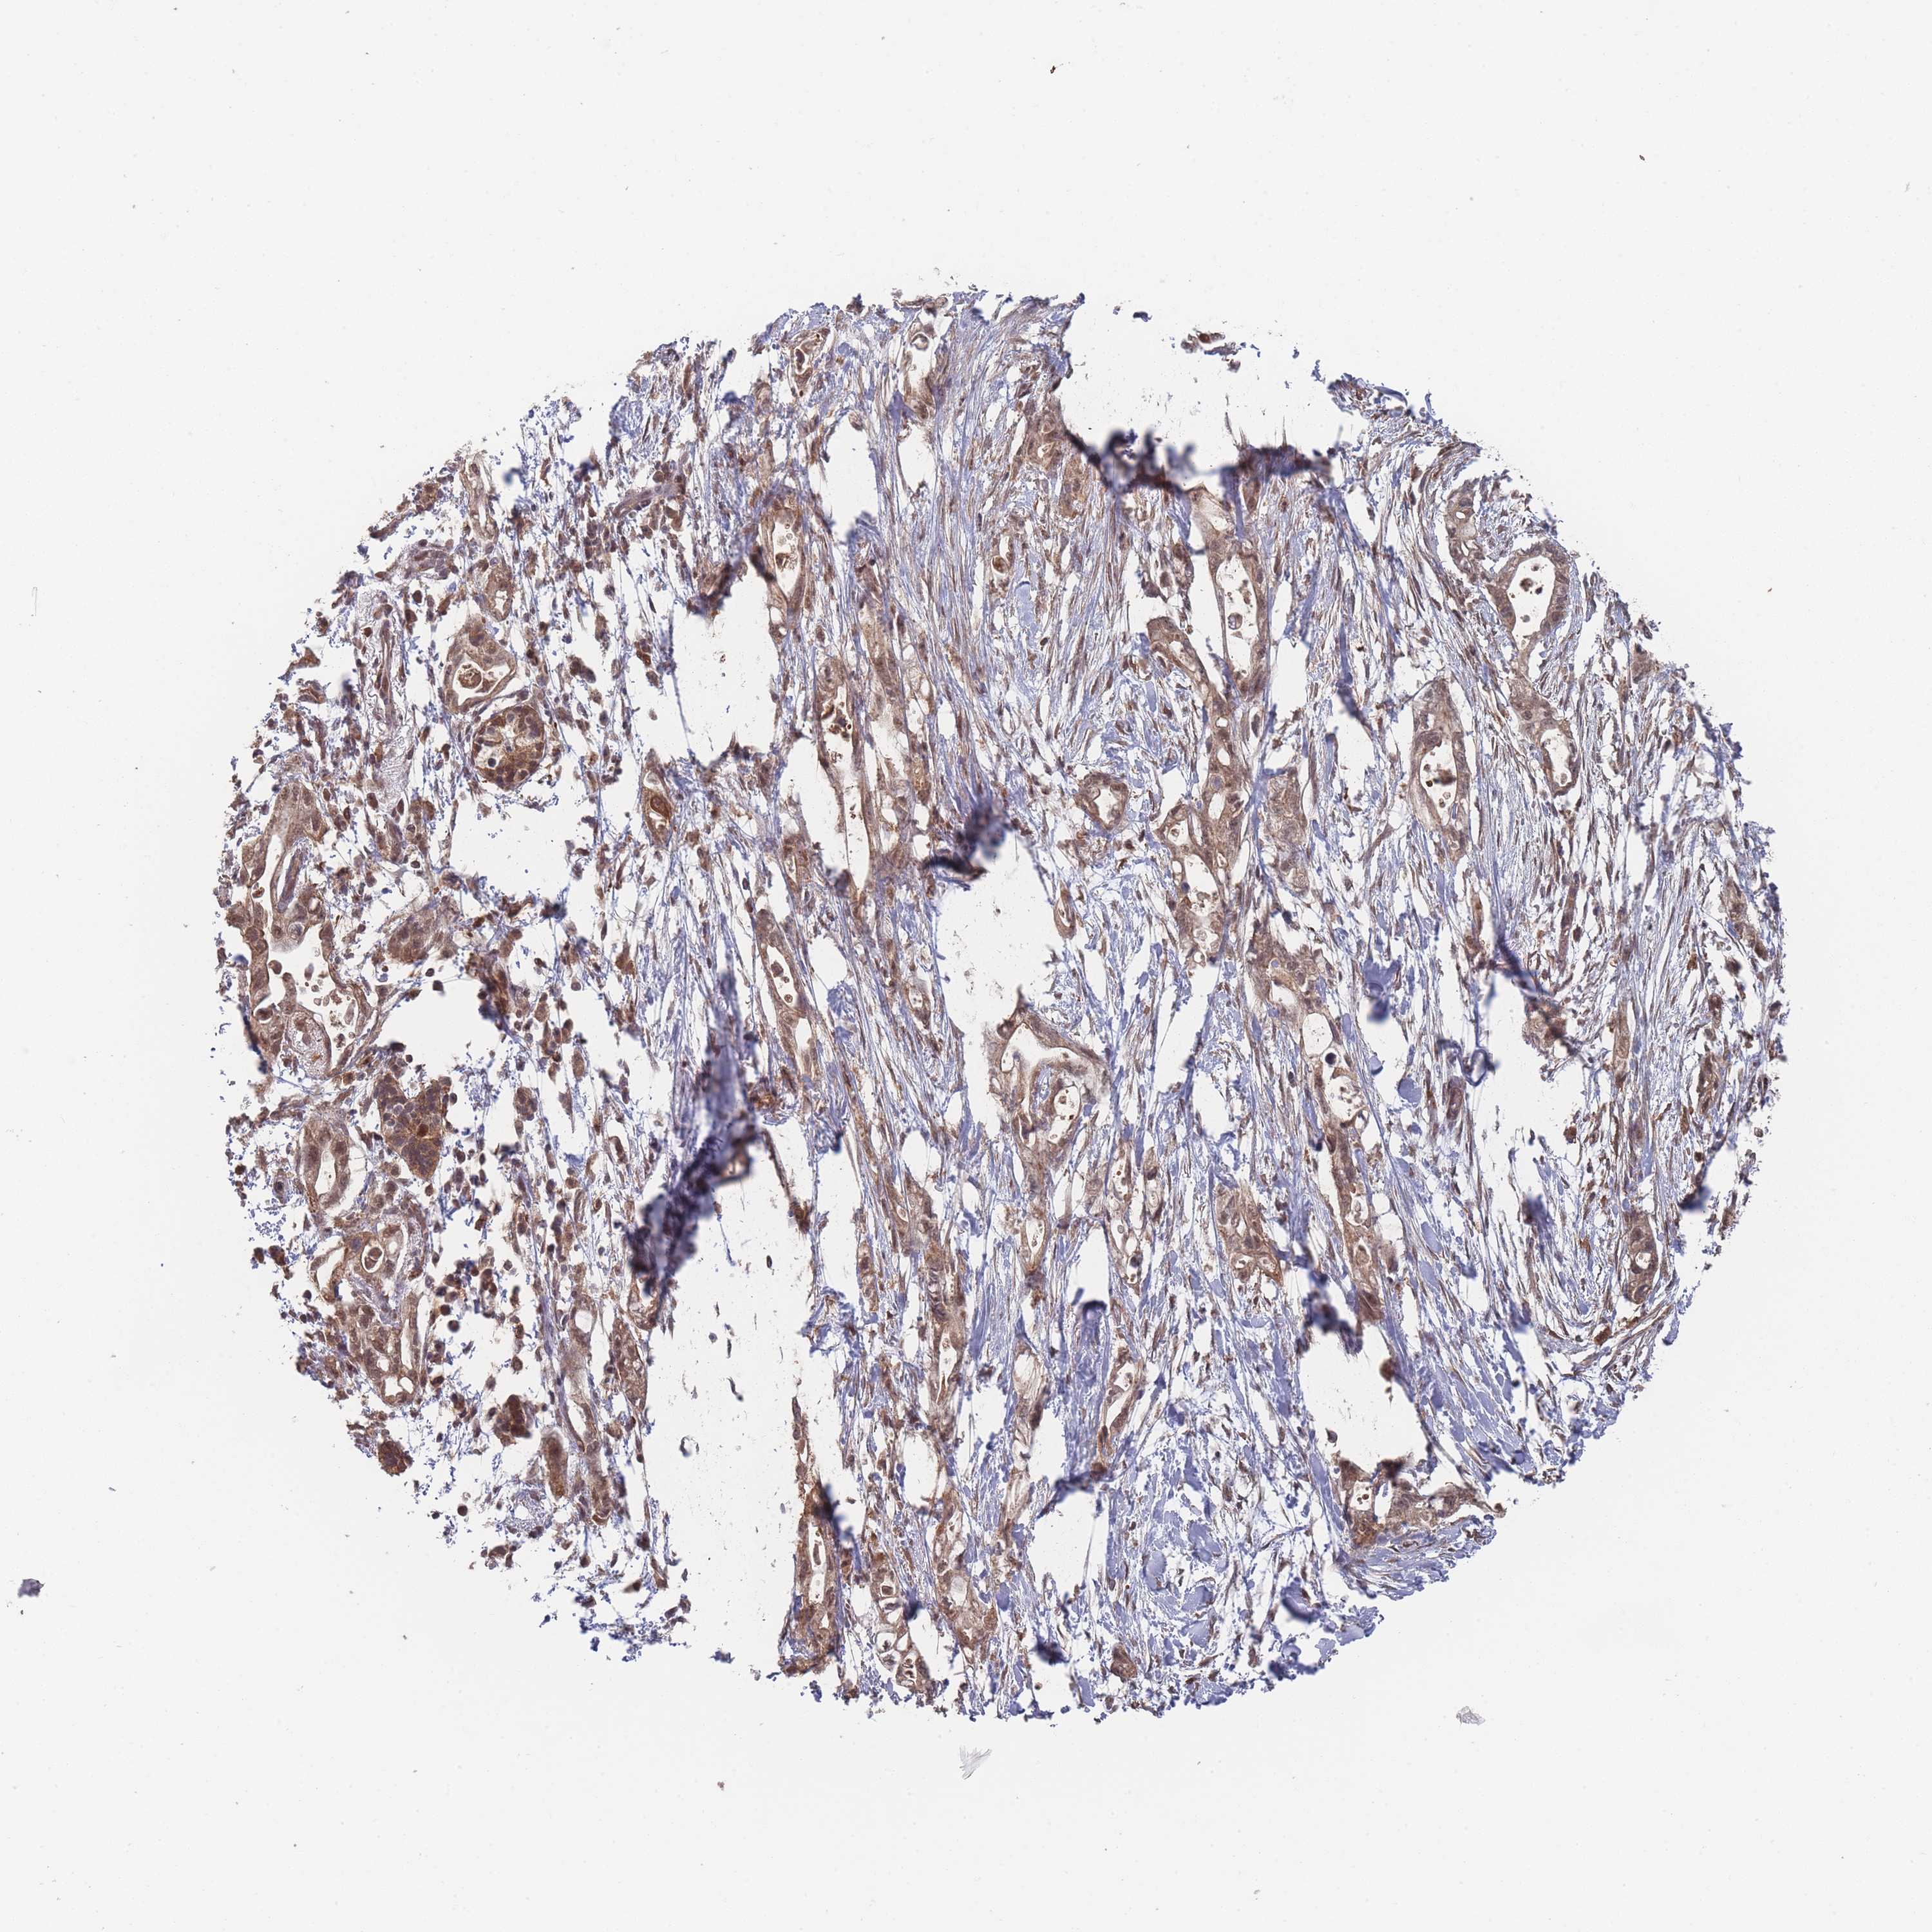

PANCREATIC CANCER - Protein expressioni

A mouse-over function shows sample information and annotation data. Click on an image to view it in a full screen mode. Samples can be filtered based on level of antibody staining by selecting one or several of the following categories: high, medium, low and not detected. The assay and annotation is described here.

Note that samples used for immunohistochemistry by the Human Protein Atlas do not correspond to samples in the TCGA dataset.

Antibody stainingi

Antibody staining in the annotated cell types in the current human tissue is reported as not detected, low, medium, or high, based on conventional immunohistochemistry profiling in selected tissues. This score is based on the combination of the staining intensity and fraction of stained cells.

Each image is clickable and will lead to virtual microscopy that enables deeper exploration of all samples and also displays staining intensity scores, fraction scores and subcellular localization as well as patient and tissue information for each sample.

Antibody HPA050275

Staining

High

Medium

Low

Not detected

Intensity

Strong

Moderate

Weak

Negative

Quantity

>75%

75%-25%

<25%

None

Location

Nuclear

Cytoplasmic/membranous

Cytoplasmic/membranous,nuclear

Adenocarcinoma, NOS